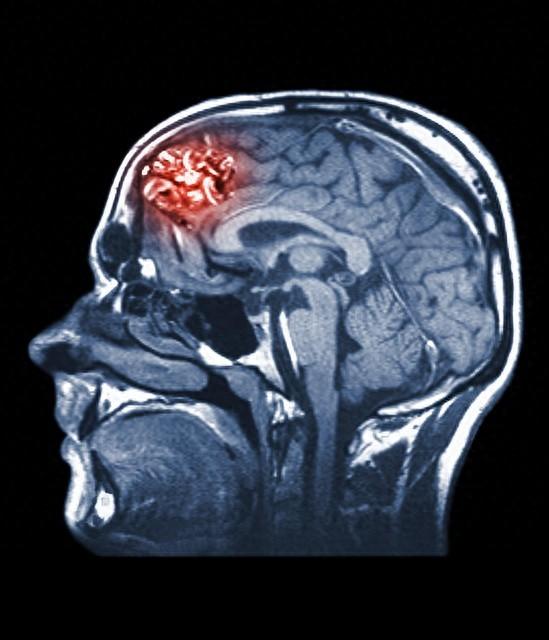

良性脑瘤能活多久(脑部良性肿瘤能活多久)

脑部良性肿瘤患者的生存时间和生活质量主要取决于几个关键因素,包括肿瘤的位置、大小、生长速度以及是否能通过手术或其他治疗方法得到有效控制。脑部良性肿瘤的一般情况1. 完全切除的可能性:- 大多数良性脑肿瘤如果能够完全切...